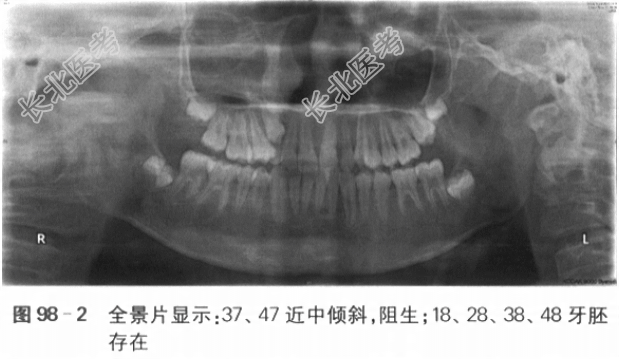

一、病历资料1.主诉前牙“地包天”3年,牙齿不齐,要求矫治。2.现病史患者男性,10岁,前牙反咬,“地包天”3年余,自觉牙齿不齐,影响美观,要求矫治。否认吐舌、吮指、咬上唇等不良习惯史,否认口呼吸史。3.既往史患者乳牙合期有“地包天”史,未进行相关治疗。否认外伤史,否认家族史。否认系统疾病史。4.临床检查(1)正面观:面部基本对称,下颌无偏斜。(2)侧面观:凹面型,下唇外翻。(3)颞下颌关节检查:张口度、张口型正常,双侧颞下颌关节未及弹响,无压痛。口内检查:混合牙列,上颌654c21~12c456,下颌76E4321~67,6近中关系,16、12、11、21、22、26反

,反覆盖浅,反覆

深,下中线左偏2mm,上牙弓狭窄,上前牙直立,重度拥挤,15腭侧错位,14、24颊侧错位,下颌3~3重度拥挤,22过小牙,口腔卫生良好,牙周健康。下颌可后退至切对切(见图98-1)。5.影像学检查6.模型分析(1)上牙弓拥挤度:未测量(13、23阻萌,15腭侧错位,重度拥挤)。(2)下牙弓拥挤度:4mm。(3)下颌Spee曲度:4mm。(4)前牙Bolton比:80.3%。(5)全牙Bolton比:92.7%。二、诊断与诊断依据(1)骨性Ⅲ类,上颌轻度发育不足,下颌轻度发育过度:头颅定位侧位片测量值显示SNA78°,SNB80°,ANB-2°,Ao-Bo-8mm,APDI95°。(2)安氏Ⅲ类:前牙反

,第1恒磨牙近中关系。(3)牙列拥挤:全景片显示上颌双侧尖牙阻萌,模型测量显示下颌拥挤度为4mm,上颌15腭侧错位。(4)13、23阻生可能。